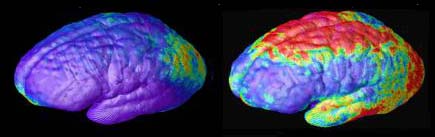

Areas of gray matter loss — shown in red and yellow — spread from back-to-front (right to left) over 5 years in composite MRI scan data from 12 teens with childhood onset schizophrenia, beginning at age 14 (left). Red and yellow denotes areas of greater loss.

Composite MRI scan data showing areas of gray matter loss over 5 years, comparing 12 normal teens (left) and 12 teens with childhood onset schizophrenia. Red and yellow denotes areas of greater loss. Front of brain is at left.